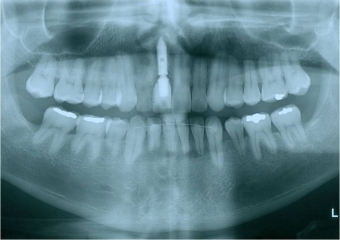

Raio X inicial